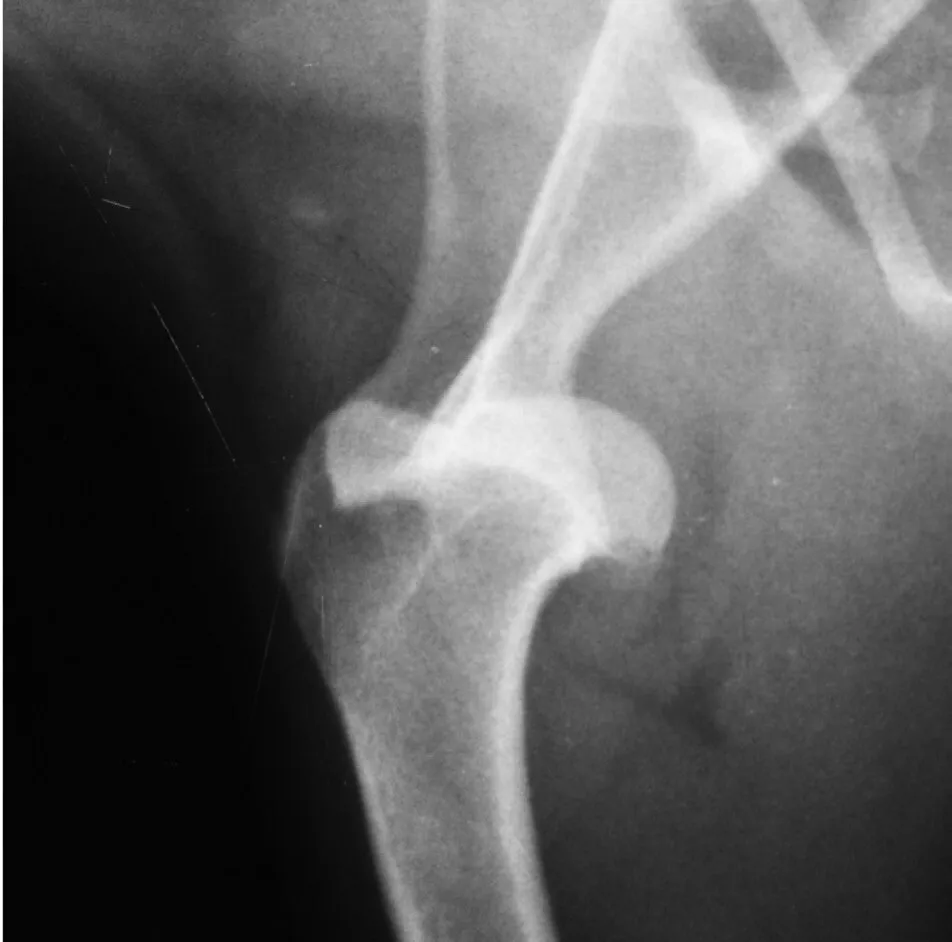

Omuz instablitesi omuz ekleminin stabil ve düzgün çalışamadığı durumları ifade etmek için kullanılır. Hastalık genellikle zorlanma ve burkulmaları takiben gelişir. Omuz instabilitesinin birkaç farklı şekli vardır. Bazı köpekler omuz bağlarında düşük dereceli tekrarlayan burkulma yaralanması veya rotator manşet kaslarında zorlanma yaralanması yaşarlar. Hastalık genellikle orta yaşlı, atletik, büyük ırk köpeklerde görünse de küçük ırk köpekler ve kedilerde de görülebilir. Hastalarda aksama genellikle egzersizden sonra kötüleşir. Bazen kalıcı belirgin bir aksama vardır.

Teşhis

Omuz instabilitesinin teşhisi genellikle sedasyon veya genel anestezi altında yapılan fiziksel muayene ile koyulur. Ayrıca eşlik eden osteoartrit varlığının tespiti için hastamızın omuz radyografilerini çekmekteyiz. Öte yandan ileri durumlarda problemin boyutunu ve şeklini daha iyi görebilmek için manyetik rezonans görüntülemeden de sıklıkla faydalanıyoruz. Omuz eklemindeki subluksasyonu da instabilite olarak değerlendirmek mümkündür.